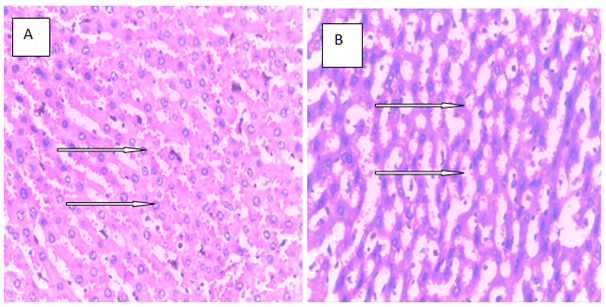

Histopathology is a critical part of the toxicologic and risk assessment of foods, drugs, chemicals, biologics, and medical devices. Histopathology is the study of the structural manifestations of disease at the light–microscopic level. Therefore, histopathology is necessarily a largely confirmative, descriptive and interpretive science. In addition to other applications, it can establish correlations between perturbations in serum biomarkers with morphologic alterations that may occur at tissue or organ levels due to a test substance.26 In the current study, histological assessment of the liver of control rats showed normal histology (Figure 1A). Also, the liver of rats treated with MT and ALA showed normal histology (Figure 1B, D). On the other hand, extensive hepatocyte necrosis was observed in the liver of LPV/r–treated rat (Figure1E), which is consistent with previous report.27 However, the liver of rats pretreated with MT and ALA showed absence of hepatocyte necroses (Figure 1G, H). This observation connotes that MT and ALA abrogate LPV/r–induced hepatic structural changes in pretreated rats. The protective effect of ALA observed in this study can be correlated with the study by Abdel Zaher et al.28 which reported that ALA restored liver structure in acetaminophen–intoxicated rats.28 Also, findings in the present study can be correlated with the reported protective effect of MT against cadmium–induced hepatic morphological alteration in rats.29 The mechanism by which LPV/r causes hepatic morphological alteration is not clear; however, it may involve OS, LPO and the stimulation of inflammatory cascade. Previous studies have reported hepatic OS leading to LPO in LPV/r–treated rats.30 OS is associated with oxidative radical production, which can result in histopathological lesions with a broad spectrum, ranging from hepatotoxity to hepatocellular carcinoma in an orchestrated manner. Evidence have shown that increased free radical concentration and activity are commonly observed during hepatic cell damage characterised by OS and LPO.31 LPO is a complex process that involves the formation and propagation of lipid radicals, the uptake of oxygen, rearrangement of double bonds in unsaturated lipids and the eventual destruction of membrane lipids.32 Exposure of hepatic proteins to reactive oxygen species can produce denaturation, loss of function, cross–linking, aggregation and fragmentation of connective tissues.33 In the current study, the protective effects of MT and ALA may be due to their free radical scavenging activities, inhibition of OS, LPO, and inflammation. Also, MT and ALA might have increased endogenous antioxidants activities and stabilized hepatic plasma membrane. ALA is a powerful antioxidant due to its ability to scavenge free radicals in both lipophilic and hydrophilic environments and to regenerate endogenous antioxidants. Also, it can inhibit LPO, OS, and prevent protein glycation and repair biomolecules damaged by oxidation.34,35 MT is an amphiphilic molecule that can freely cross cell membranes and enter cells where it has been reported to alter redox balance by increasing antioxidant synthesis, activity and scavenges free radicals. It can inhibit LPO thereby preventing DNA, lipid, and protein damage.36 Furthermore, experimental evidence showed that MT and ALA can inhibit inflammation–induced hepatotoxicity by up regulating anti–inflammatory mediators and inhibiting pro–inflammatory mediators.37,38

Figure 1 The above figures (A–G) are micrographs of the Hand E stained sections of the liver of control rat, and the liver of rats in the experimental groups. Normal hepatocytes were observed in the liver of control rat Figure 1A. Also, normal hepatocytes were observed in the liver of rats treated with melatonin, alphalipoic and a combination of melatonin, and alphalipoic (Figures 1E). On the other hand, extensive hepatocyte necrosis was observed in the liver of lopinavir/ritonavir-treated rat Figure 1E. However, normal hepatocytes were observed in rats pretreated with individual dose of melatonin and alpha lipoic acid respectively Figure 1F and G. Also, normal hepatocyte was observed in the liver of rats pretreated with a combination of melatonin and alpha lipoic (Figure 1H).